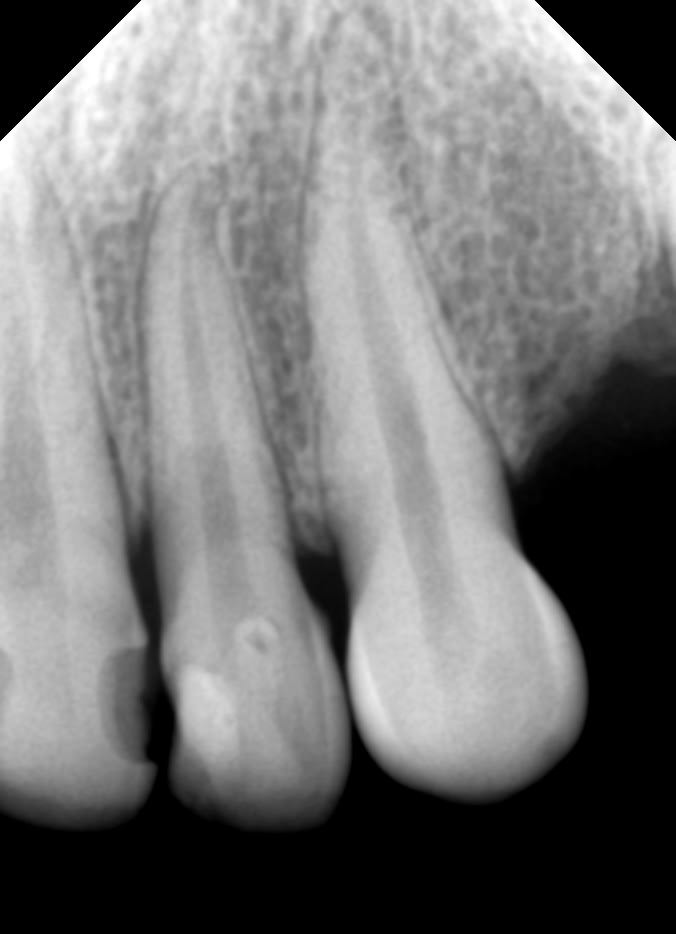

1. Oui, pour le Vatech, sur Win7. Tu implémentes sur ton ordi le logiciel Easydent V4 à l'aide du cd fourni . Et c'est tout. Mon logiciel de gestion du cab fait le lien automatiquement.

2. Oui, il y a trois ans. Avec quelques craintes au départ, mais tout c'est passé normalement. Et cela marche toujours aujourd'hui (on est hors période de "garantie", donc).

Une bête radio faite ce matin. C'est suffisamment lisible je crois, il n'y a ici aucune retouche effectuée,mais le logiciel le permet.